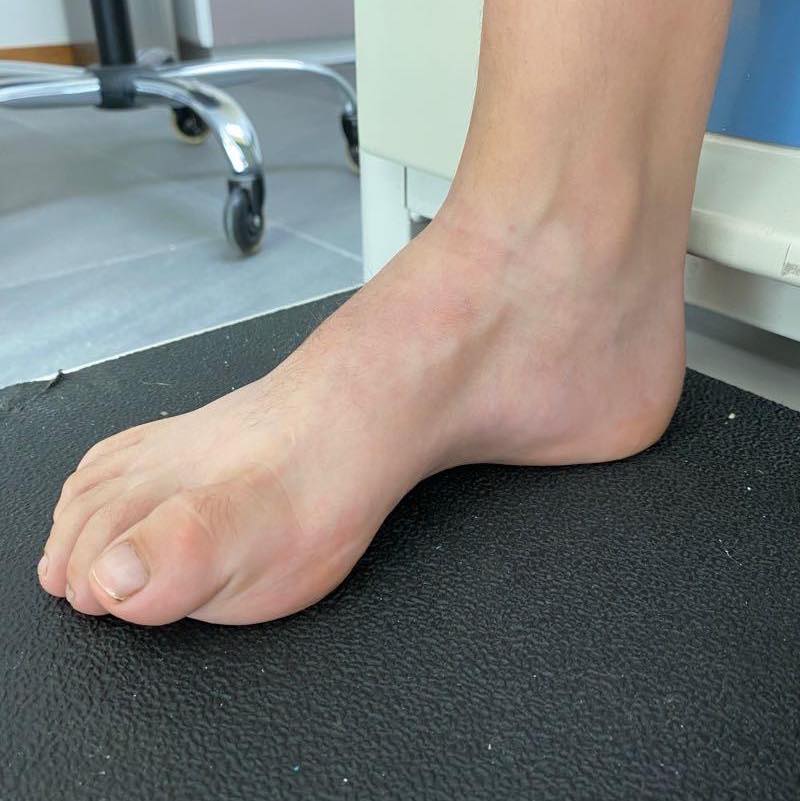

Pie plano infantil

El tratamiento debe ser enfocado solo a aquellos pies que sean dolorosos y que presenten una deformidad importante que impida el uso de calzado habitual. El mejor tratamiento es la rehabilitación y para aquellos que sean rígidos será necesario estudiarlos para descartar la coalición tarsal o alguna otra enfermedad.